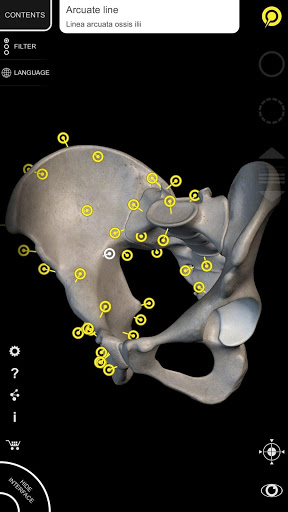

"Anatomía - Atlas 3D" permite estudiar la anatomía humana de forma fácil e interactiva.

A través de una interfaz sencilla e intuitiva es posible observar cada estructura anatómica desde cualquier ángulo.

Los modelos anatómicos 3D son especialmente detallados y con texturas de hasta una resolución de 4k.

La subdivisión por regiones y las vistas predefinidas facilitan la observación y el estudio de partes individuales o grupos de sistemas y las relaciones entre los diferentes órganos.

MODELOS ANATÓMICOS 3D

• Sistema musculoesquelético